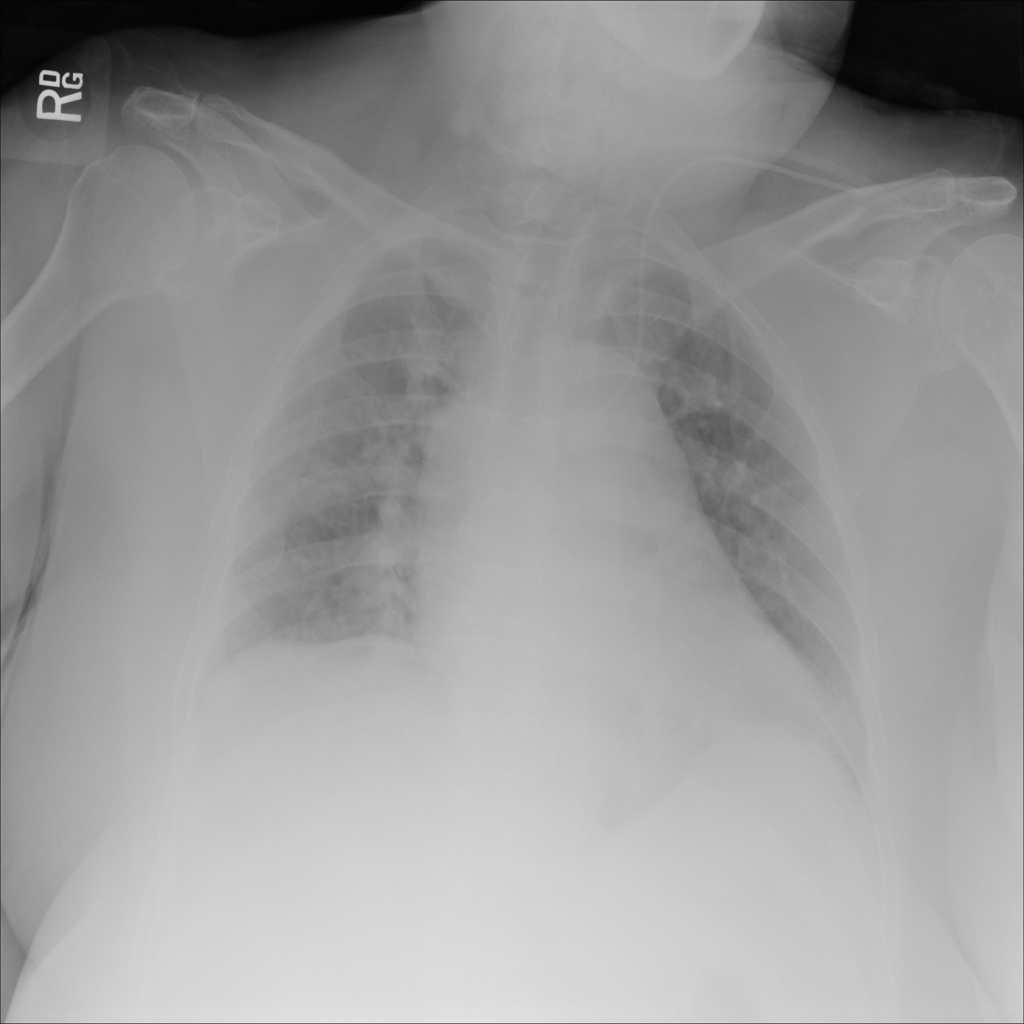

PAT-A1E2 · IMG-001Pneumonia

PAT-A1E2 · IMG-001

AP